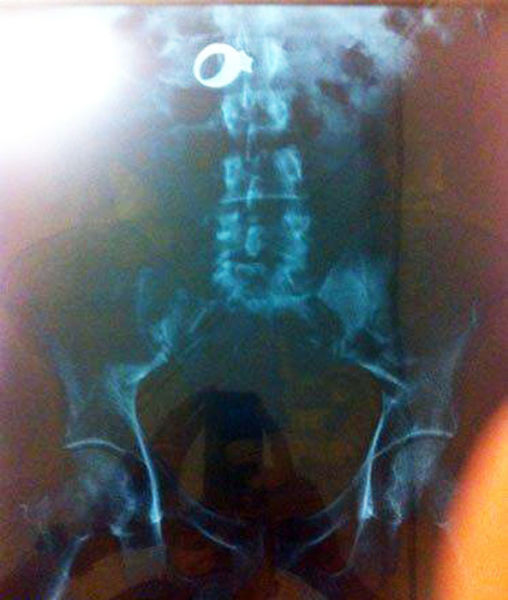

This X-ray reveals a cell phone lodged in a Salvadoran prisoner's lower intestine. The man is one of four prisoners who are members of the Mara Salvatrucha street gang. The men were caught with cell phones, spare chips and a charger that they had attempted to smuggle, according to authorities at San Salvador's Zacatecoluca prison.